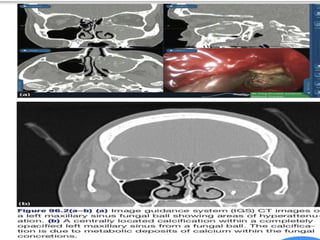

๏‚— Radiological findings of sinus opacification often with

areas of hyperattenuation.

๏‚ง Usually unilateral

๏‚ง Involves the maxillary sinus

๏‚ง Well defined, high attenuation mass

๏‚ง Occasional flocculent Ca

๏‚ง Reactive sclerosis of sinus wall

๏‚ง No invasion

f ๏‚ง Usually unilateral ๏‚งInvolves the maxillary sinus ๏‚ง Well defined, high attenuation mass ๏‚ง Occasional flocculent Ca ๏‚ง Reactive sclerosis of sinus wall ๏‚ง No invasion Fungal ball